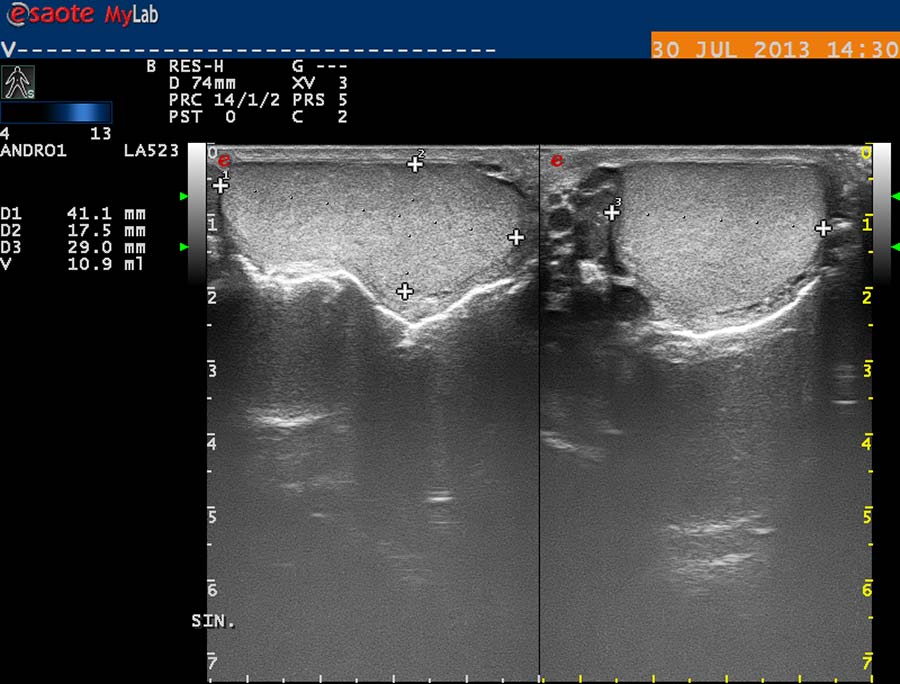

USG diagnostika vyžaduje odpovídající vybavení (obr. 12), zkušenosti a dostatek času. Vyšetření USG provádíme po termografickém vyšetření, na lůžku vyhřívaném na 30 st. Celsia, ultrasonografický gel zahříváme ve vodní lázni na teplotu 35 stupňů. Chladová kontrakce musculus cremaster vede k falešně negativním nálezům. Základní projekcí je koronární sken varlete (obr. 14) následovaný volumometrií ve dvou rovinách (obr. 15). Již na těchto skenech varlete je patrné rozšíření intratestikulárních cév, lépe je však viditelné při harmonickém („tissue enhancement imaging – TEI“) zobrazení (obr. 16, 17), a při barevném Dopplerovském zobrazení (Power Doppler) s TEI (obr. 18) s měřením šíře stěny a lumen žíly. Objemné dilatované žíly pampiniformního plexu jsou velmi dobře patrné na kolorizovaném TEI zobrazení (obr. 19), kde je možné zachytit pohyb venózní krve v souvislosti s dechem, intraabdominálním (IAP) a intrathorakálním tlakem. Informaci o atrofizaci tkáně získáme ze záznamu deformace kontury tunica albuginea podložkou, kterou je měkká buničina vložená pod skrotum (obr. 20, obr. 21 s volumometrií). Triplexní Dopplerovský záznam umožní hodnotit délku žilního refluxu a rychlost proudu refluktující krve v inspiriu, reflux při zvýšení intraabdominálního tlaku (obr. 22,23). Duplexní Dopplerovský záznam při harmonickém zobrazení s kolorizací zachycuje senzitivně změnu rychlosti proudění při refluxu v inspiriu s navazujícím zvýšením rychlosti při IAP (obr 25). Významná je možnost zachycení refluxu při klidném dýchání (respirační reflux, obr. 26).

obr. 15